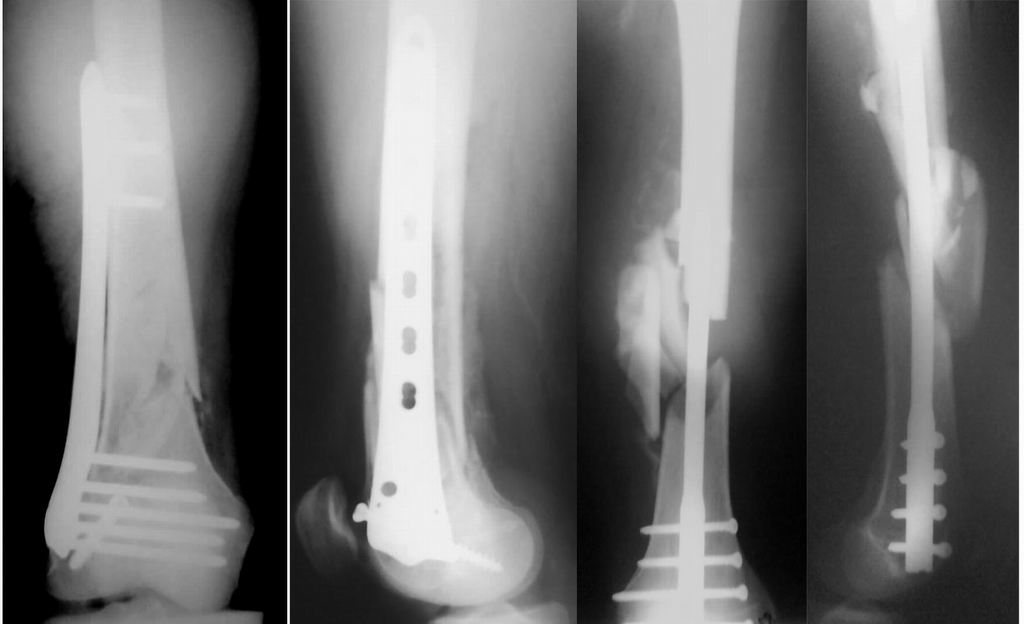

Привет из Нижнего Новгорода! К нам поступил пациент 25 лет с закрытыми переломами обеих бедренных костей, прошел месяц после травмы. Слева - внутрисуставной перелом, поэтому выбор здесь очевиден, открытая репозиция, стабильная фиксация, скорее всего LCP DF, а справа - мнения учёных, как говорится, разошлись. Лично я, как лечащий врач, за закрытый интрамедуллярный остеосинтез DFN. Со мной согласна половина коллектива, другая - за интрамедуллярный остеосинтез (DFN,UFN) но с открытой реопозицией, поскольку при закрытой методике все осколки останутся где-то сбоку, получится дефект и вдруг не срастется!Философский вопрос: что лучше - красивая рентгенограмма или сохранение кровоснабжения? Очень важно мнение коллег! Смирнов Алексей

Мы бы не стали открывать, такие переломы срастаются, хотя бы и с краевым дефектом. То есть если удалять стержень потом, то сильно попозже обычного. В приложении пример. Сразу после операции и через 11 мес. Понятное дело, пациент к тому времени давно и не хромал, и функция колена была полная.

Уважаемые коллеги! От имени Алексея Смирнова всем спасибо за обсуждение. Больной прооперирован. Снимки в приложении.